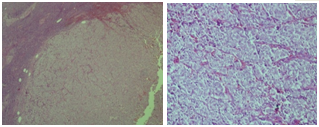

A 59 year old female admitted to emergency medicine service of Canakkale State Hospital with confusion. She had comorbidities as chronic obstructive pulmonary disease (COPD) and hypertension. She had been treated with inhaler ß2 agonist and angiotensine converting enzyme inhibitor therapy. One month ago she admitted to internal medicine polyclinic with polyuria and polydipsia complaints continuing for a few months. Plasma biochemistry showed: impaired fasting glucose (glucose: 109 mg/dl, HbA1c: 6.1%), hypochromic microcytic anemia, erythrocyte sedimentation rate increased; serum electrolytes, renal and hepatic function test results were normal. Physical examination was normal except left cervical lenfadenopathy. Ultrasonography (USG) signs of lymph node was malign features; therefore excisional biopsy was performed and undifferantiated carcinoma metastasis was showed (Figure 1). In investigations to find primary malignancy mammography, breast USG, abdominal USG and thorax computed tomography (CT) were normal; only in abdominal CT rectal wall was thickened.

Figure 1 Solid foci of undifferentiated tumor cells inside normal lenfoid tissue and rarely seen primitive adenoid cells.